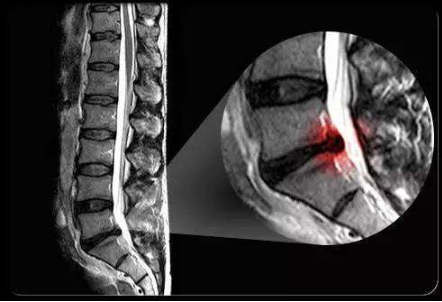

坐骨神經痛

X線、CT、MRI檢查

坐骨神經痛圖片